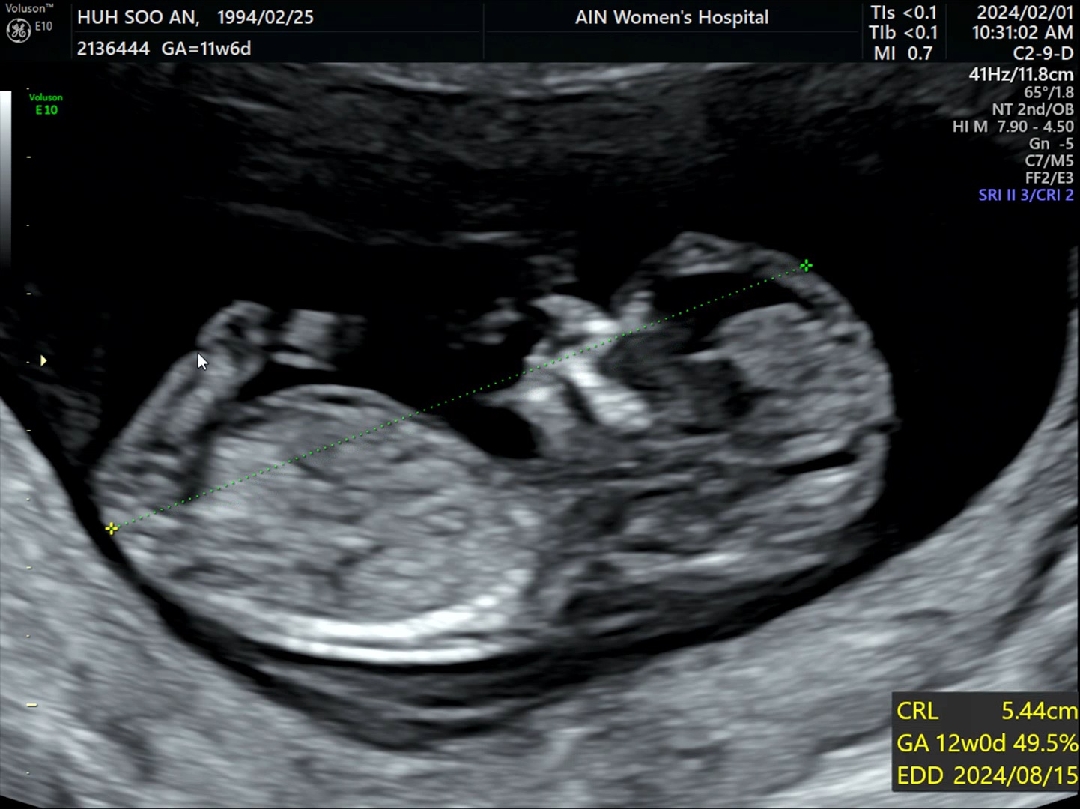

각도법은 일반 초음파로 옆모습이 잘 나와야해요!(no입체초음파, no정면)

오랜만에 베동 들어오니 각도법 이야기가 많네요 ㅋㅋ 각도법 볼 때 사진만으로는 정확하게 보기 어렵고 옆모습이 선명하게 잘 보여야 가능하대요 ㅎㅎ 입초 말고 일반 초음파 옆모습으로 된 사진+영상이어야 가능하구요 ㅎㅎ (사진으로는 볼 수 없던 아기 성기 각도와 척추각도, 꼬리뼈 각도 등 여러 각도를 동영상으로 봐야 좀 더 정확하게 유추할 수 있대요) 네이버 카페 "장꾸맘의 각도법" 여기 가셔서 여쭤보세요! 각도법으로 유명한 분인데 엄청 잘 맞추세요! 저도 여쭤봤는데 아들에 한 표 주시더라구요 ㅋㅋㅋ